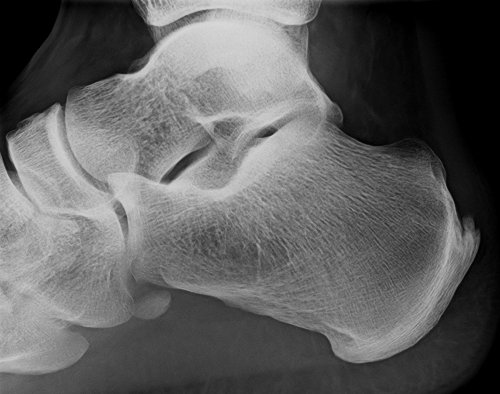

Behandlungsbeispiel

Die Orthovolttherapie ist eine schmerzfreie, nichtinvasive Behandlung mit speziellen energetischen Röntgenstrahlen.